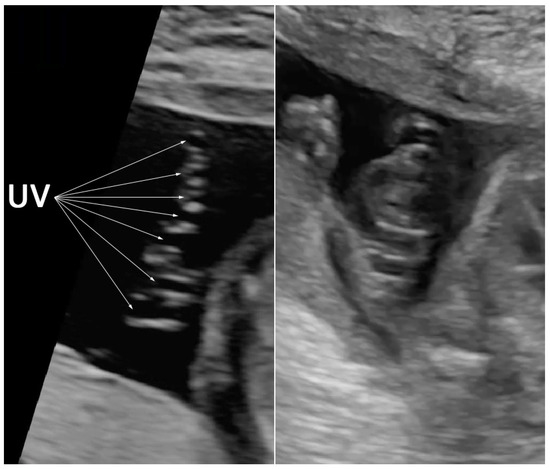

2. Case Presentation